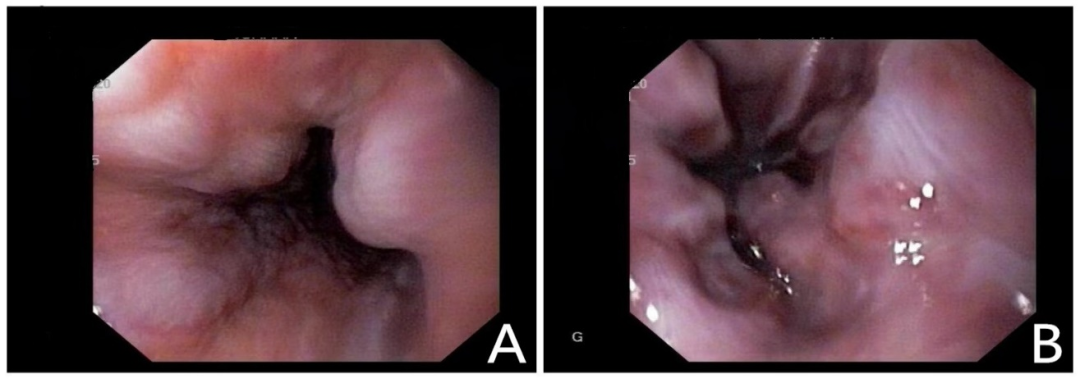

乙肝肝硬化患者合并肝门部胆管狭窄致梗阻性黄疸罕见病因1例

病史摘要:患者为 38 岁男性,因“发现乙肝 1 月余,腹痛 1 天”入院。1 月前诊断为“失代偿期肝硬化(脾大、腹水、门脉高压、食管静脉曲张)乙肝”,经抗 HBV、保肝治疗后症状缓解。入院前 1 天突发剑突下疼痛,进食后稍缓解,入院当日腹痛加重,伴恶心、呕吐。有吸烟及不规律饮酒史,现已戒酒,母亲因“肝硬化”去世,无慢性基础疾病、手术史、过敏史及有毒有害物质接触史。